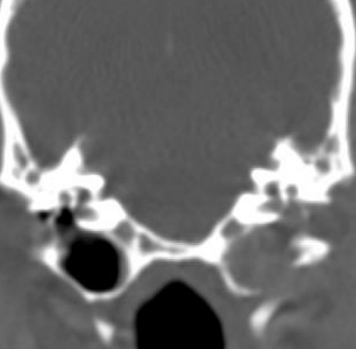

| Radiographs & CT | |

| - Open mouth view → 방사선 - 칼슘화 확인 | ==CT : tympanic cavity, 중이== 확인 - 정상일 때는 연골이 크게 변하지 않지만, 칼슘화되면 많이 변함. - 심각할 때 (많이 부어있고, 이도 막혀 있고, 냄새 나고 등) CT를 통해 중이를 확인해야 함. - vertical/horizontal ear canal의 mass 확인 등 | |

- 방사선, CT : concurrent otitis media, calcification, bone lysis (neoplasia)

왼쪽 tympanic cavity 는 정상 / 오른쪽은 꽉 막혀 있고, 뼈도 없음.